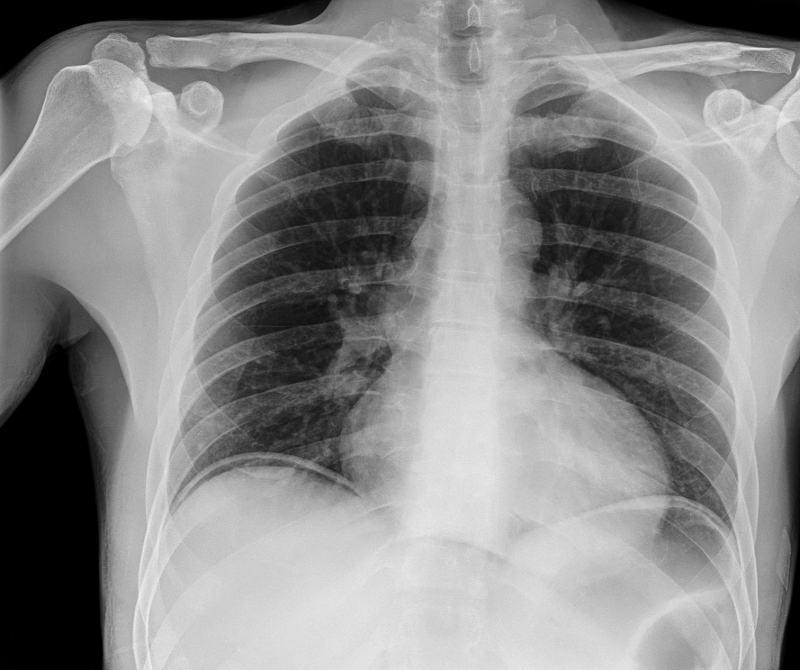

Bolsas de ar livre abdominal, radiografia

Science Photo Library; usado com permissão